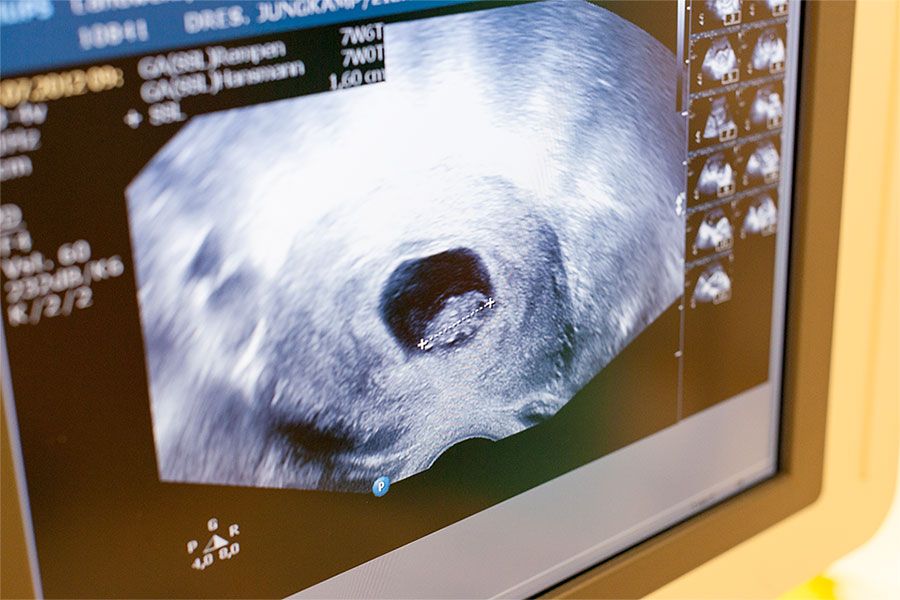

Neben der üblichen Mutterschaftsvorsorge bieten wir Ihnen zusätzliche Labordiagnostik sowie differenzierte Ultraschall-Untersuchungen an, z.B. Ersttrimesterscreening (zertifiziert nach der Fetal Medical Foundation Deutschland e.V.), erweiterte Organdiagnostik sowie 3D-Ultraschall.